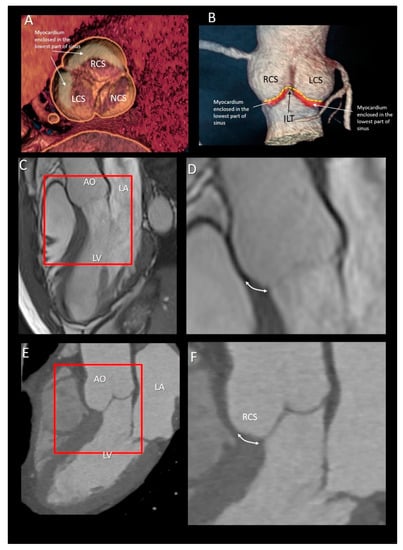

| Ventricular–arterial junction | The term ventricular–arterial junction describes the border between the ventricular myocardium and the fibroelastic structure of the aortic root. Contrary to the right AV junction, where the pulmonary root is entirely supported by the muscular infundibulum, only the left and the right coronary sinuses are partially supported by the myocardium (see text), being the remaining extent of the aortic root supported by fibrous tissue (MS = membranous septum; see text and references [12,13]). | ![]() |